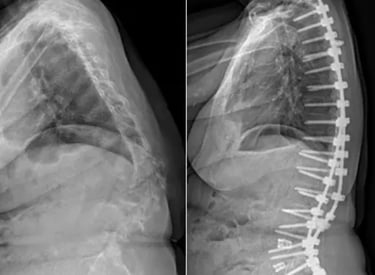

Complex Spine Problems and Deformity Correction

Specialized care focused on improving quality of life and restoring your ability to return to daily activities

Gallery

Explore our advanced spine care techniques.